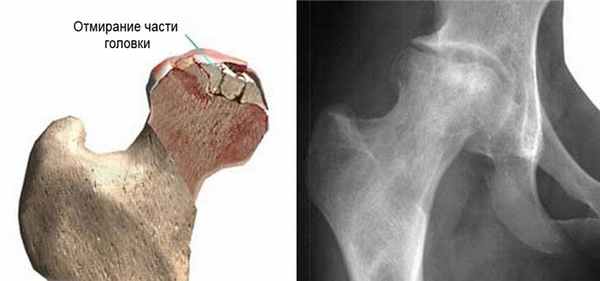

Асептический некроз кости - заболевание, при котором происходит отмирание (некроз) костных участков и костей в целом в результате нарушения или полного прекращения кровотока в определенном участке кости. Идиопатический асептический некроз развивается самопроизвольно без особых на то причин. Встречаются полный и частичный некрозы кости, а также различают поверхностный и глубокий некроз в зависимости от его локализации в кости. Болезнь протекает в несколько стадий.

Первые симптомы асептического некроза могут появляться не сразу. Иногда после перенесенной травмы могут пройти месяцы, и даже годы. Имеют место следующие симптомы: болевой синдром при движении, который может приводить к мышечной контрактуре; атрофия мышц; ограничение подвижности больной части тела; укорочение конечностей.

Кисты и некрозы костей можно диагностировать с помощью следующих методов:

- Осмотр врача (сбор жалоб, пальпация больного места) пораженной кости в нескольких проекциях или магнитно-резонансная томография (МРТ)